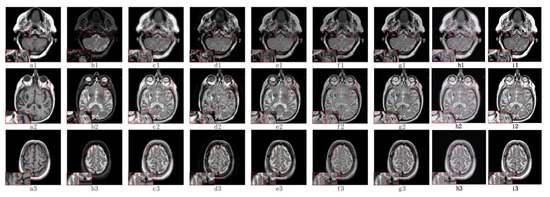

5.2.1. Fusion Analysis on T1-T2

5.2.2. Fusion Analysis on T2-PD

5.2.3. Fusion Analysis on CT-MRI